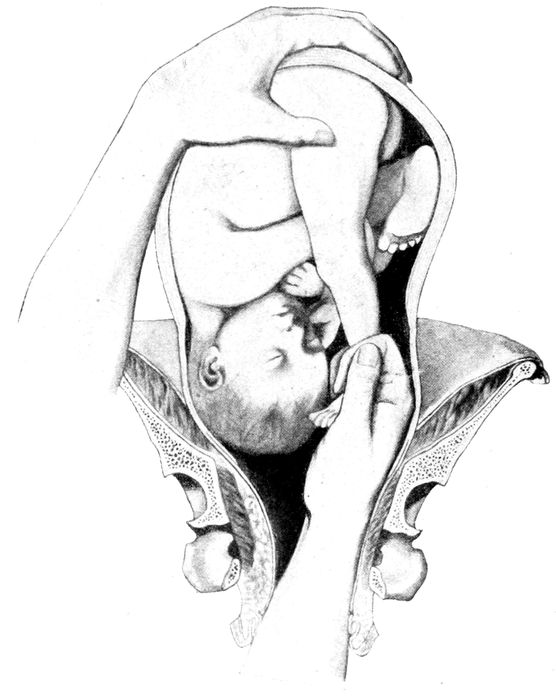

Extraction of the breech |

170 |

| |

| 64. |

Breech delivery. Extraction of the trunk |

171 |

| |

| 65. |

Breech delivery. Delivering the shoulder |

172 |

| |

| 66. |

The delivery of the after-coming head by the Smellie-Veit maneuver |

172 |